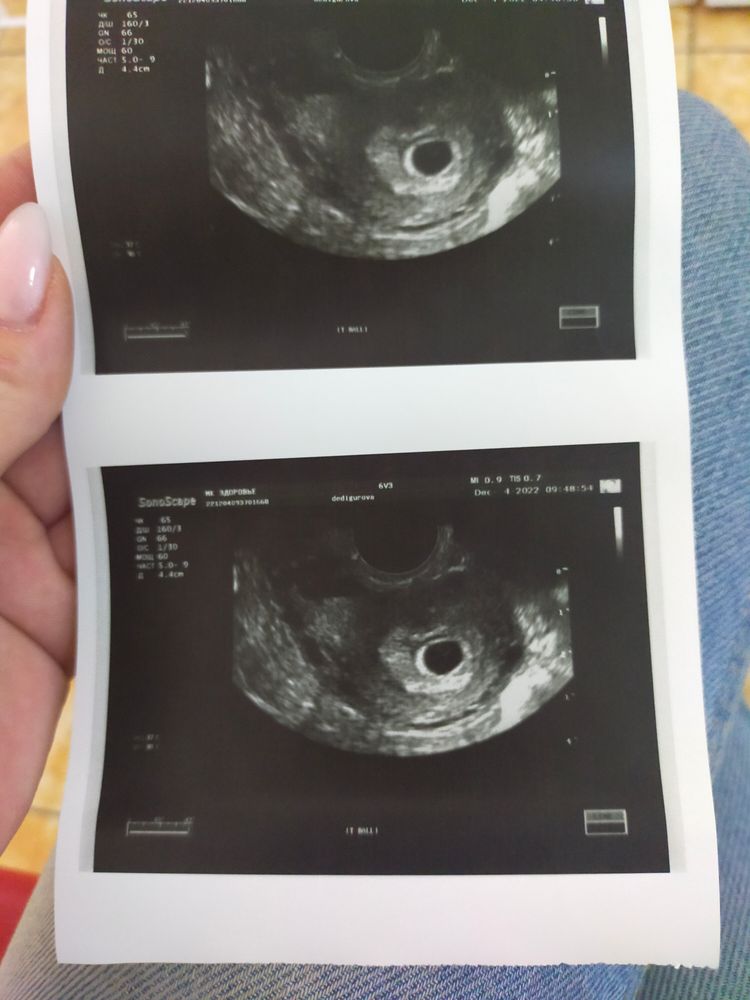

Девочки, такой вопрос, задержка месячных уже 10 дней, тесты полосятся без раздумий, сегодня на УЗИ показало жёлтое тело в левом яичнике, срок около 6 недель, но сердцебиение не прослушивается. Норма ли это? Я уже вся испереживалсь

Последние м были 23 октября, цикл 29 дней

Елена, врач-узист сказала, что видит эмбриончика, но прям очень-очень маленького, мне не разглядеть было уж точно. Возможно, овуляция была поздняя, и срок меньше 6 недель, поэтому и нет ещё сб, накручиваю себя, первая беременность, все дела...

Настя Дедигурова, на фото просто пустой шарик)

А про желточный мешочек ничего не говорили? Если видит эмбриончика, значит через неделю подрастет. А у такой крошечки и СБ то не увидят.